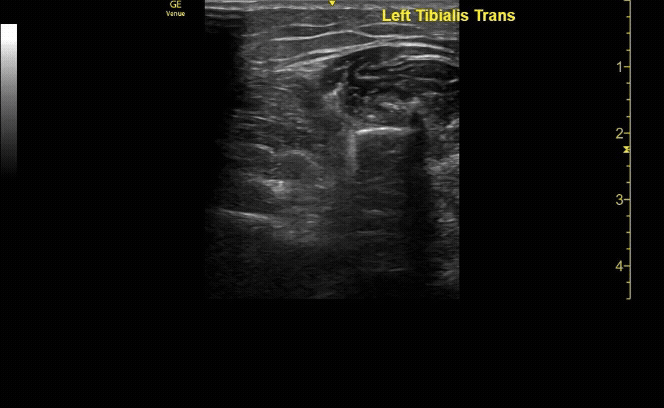

Affected tibia in transverse view.

c/o Santiago Tovar, MD